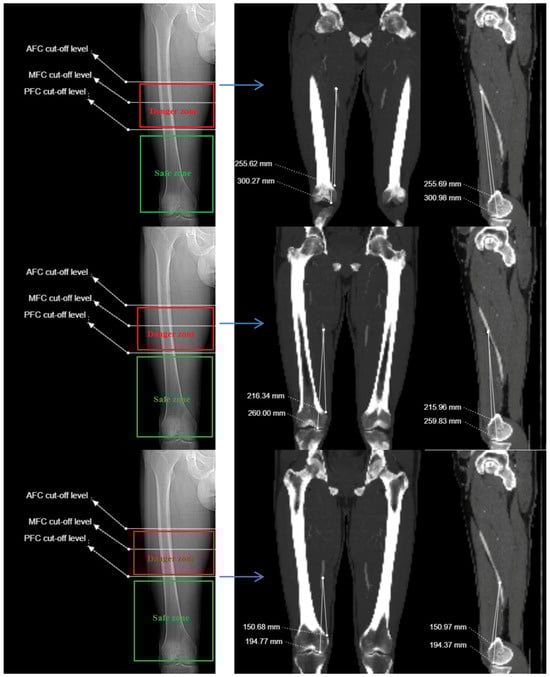

2.3. Imaging and Measurement Methods